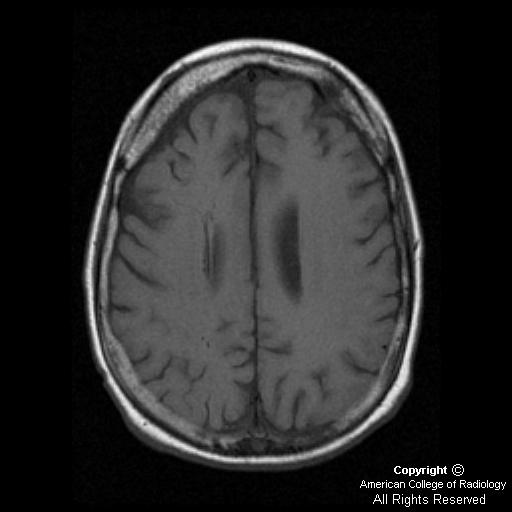

Neurocutaneous syndromes are a diverse group of disorders that involve both skin and nervous systems. It is typically located in the occipital lobe. Mri features include leptomeningeal angiomatosis, cortical and pial calcifications, and angiomatous change of the choroid plexus.

Sturge weber syndrome is a congenital condition characterized by an intracranial vascular anomaly, leptomeningeal angiomatosis, most often involving the occipital and parietal lobes.

Ct scan may show brain atrophy calcification and ipsilateral choroid plexus enlargement.

2 the calcifications do not usually appear until the patient reaches at least 2 years of age, and then they stabilize by the second decade of life.

35 year male presented with h/o frequent fall , seizures & abnormal cognitive state. It is characterized by a congenital facial birthmark and neurological abnormalities. Tram track calcification in sturge weber. Tram track sturge weber syndrome.